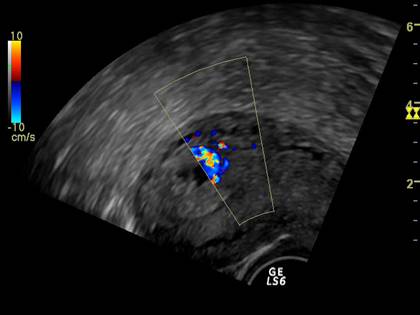

Fig nr. 71. Decolare de pol inferior recenta, la o pacienta cu metroragie si prezenta fluxului sangvin la eco Doppler ( sageata )

Fig. nr. 7 La nivelul hematomului retroplacentar se observa intreruperea circulatiei sangvine uteroplacentare ( sageata). Fluxul sangvin la Doppler, prin cordon ombilical, indica o sarcina in evolutie